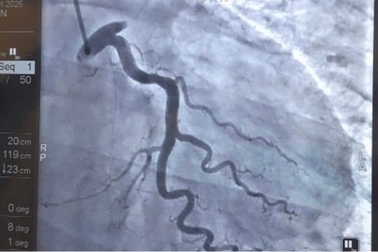

Cứu bệnh nhân người Trung Quốc nhồi máu cơ tim khi đang chơi cầu lôngChỉ trong vòng chưa đầy 1 giờ sau khi xuất hiện cơn đau ngực dữ dội, bệnh nhân nam quốc tịch Trung Quốc, 42 tuổi, đã được cấp cứu và can thiệp mạch vành khẩn tại Vinmec Hải Phòng, thoát khỏi nguy cơ tử vong do nhồi máu cơ tim.